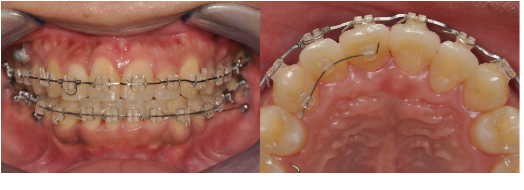

20대 남성 환자로, 입천장 쪽에 과잉치가 맹출되어 있었고 오른쪽 앞니가 180도 회전된 상태였습니다.

→ 과잉치를 발치하고 교정치료를 통해 앞니 배열을 정상화했습니다.